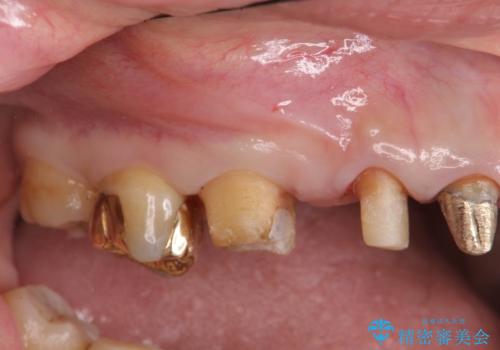

歯周ポケットの除去を併用したセラミック治療

- 歯周病や虫歯、歯の欠けなど多数の問題を他院で指摘され、今後長く持つように歯の問題をしっかりと解決したい。と希望され来院されました。

適合や審美性に優れるセラミック治療を行う前に、歯周病の問題を歯周外科を行うことで解決し将来的に不安のないような口腔内環境を整備していきます。

治療前に4-5mm程度あった歯周ポケットは全て2mm以内となり、非常に清掃性が高く、歯周病の再発しずらい環境に整えた上でのセラミック治療を実践することができました。